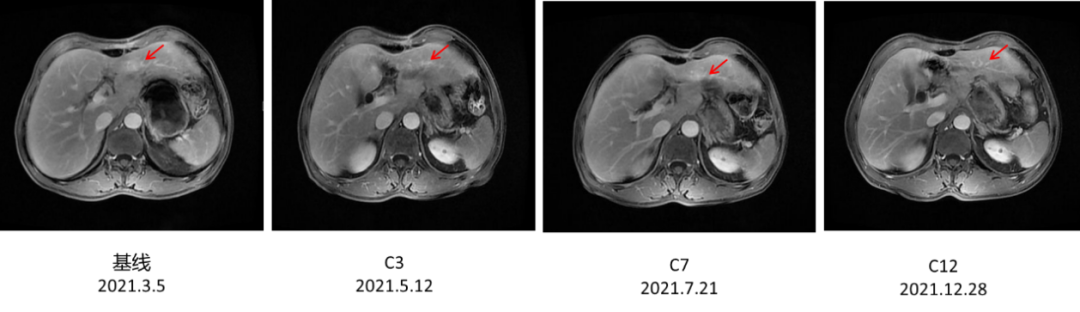

2021年3月5日术后化疗时上腹部增强MRI发现疾病进展,出现新发肝转移癌。MRI示:胃体积减小,肝脏局部体积减小,肝左叶见一类圆形轻度环形强化影,平扫显示不清,最大径约16.6mm。诊断建议:肝、胃术后改变,肝左叶环形强化影,新发肝转移。(图4)

图4. 上腹部增强MRI

2021年5月12日、7月21日和12月28日:上腹部MRI示:肝、胃术后改变,肝左叶环形强化影,体积较前逐渐减小(最大径分别为15.8mm、14.8mm、10.6mm)。(图5)

图5.上腹部MRI

汉曲优®Ⅲ期临床研究[3]结果显示,汉曲优®与原研曲妥珠单抗疗效等效,安全性、免疫原性相似,曲妥珠单抗生物类似药得到NCCN-GI指南、CSCO-GI指南的用药推荐,2020年《中国生物类似药专家共识》也指出:生物类似药与参照药疗效等同、安全性相似,临床上可以替代使用。在本病例中,患者综合经济因素等原因,在使用原研曲妥珠单抗7周期有效后,转换为曲妥珠单抗生物类似药(汉曲优®)继续治疗,目前已使用10周期,并于2021年12月28日复查上腹部MRI示:肝、胃术后改变,肝左叶环形强化影,体积较前逐渐减小,达到PR,显示出良好的疗效和安全性。